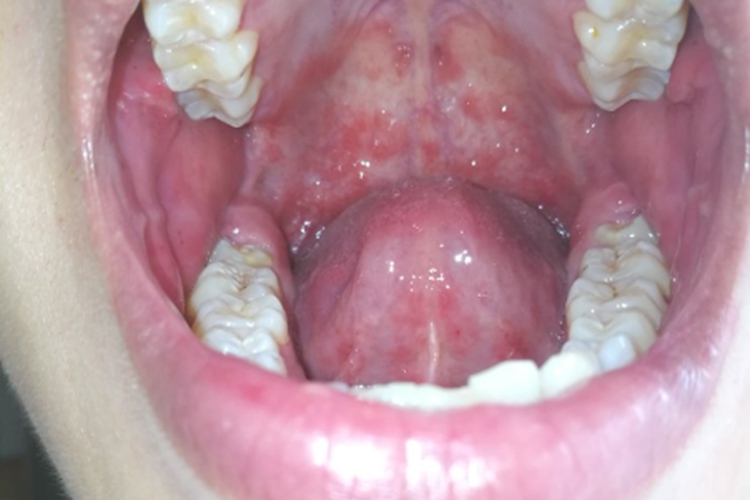

孩子上牙膛有一片红血点可能是机械损伤、过敏反应、口腔炎症、病毒性疾病、血液系统疾病等所致,应根据具体病因采取相应措施,家长应仔细观察孩子的症状,必要时及时带孩子就医,明确原因,以便进行有效的治疗和护理。

4、病毒性疾病:如手足口病、疱疹性咽峡炎等,可能在牙膛形成红血点,可能伴有发热、咽痛等症状。应遵医嘱进行抗病毒治疗,并注意隔离,防止传染。